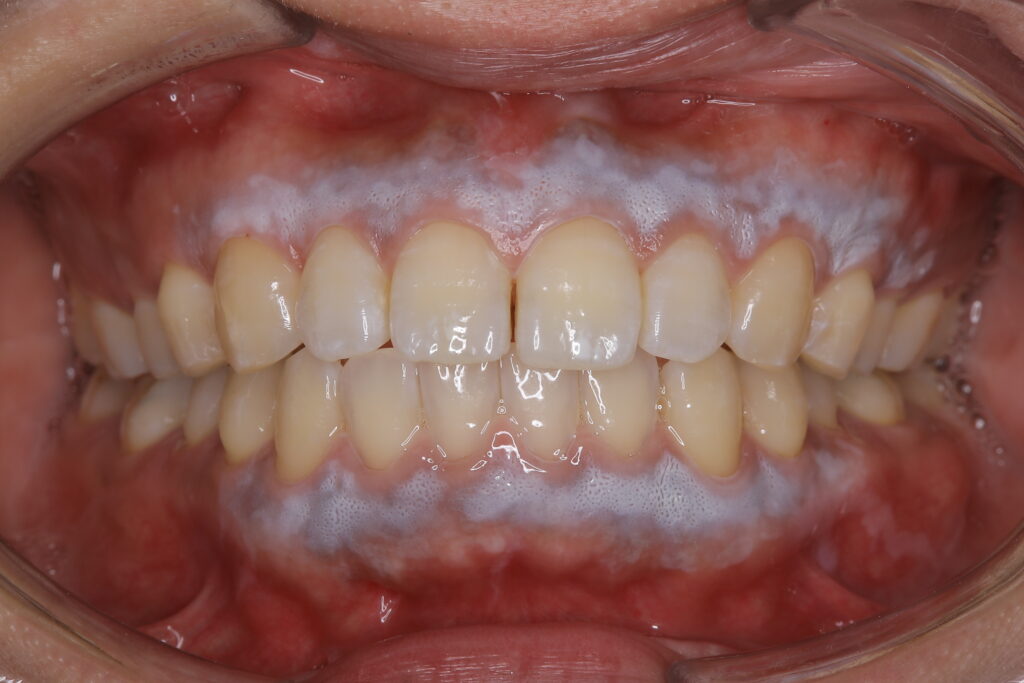

5. 術後1週間

治療後、数日から歯茎は徐々にむけ始め、最終的に美しいピンク色の新しい歯茎が現れます💡

1週間後には痛みもほとんど無くなりました。